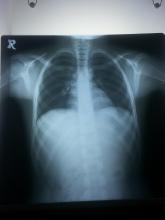

A foreign body (FB) inhalation is a common event, especially among children and young adults. Two metallic FB inhalations in children have rarely been described. The authors report the child's case who presented to the accident and emergency department with a two-hour history of choking and coughing while playing with his sister. There were no signs of respiratory distress. A plain chest x-ray demonstrated double radio-opaque shadows inside the RT bronchus intermediate. A rigid bronchoscopy was performed under general anesthesia, and the two metallic objects were removed. The procedure was uneventful and the child was discharged six hours after in good general condition.